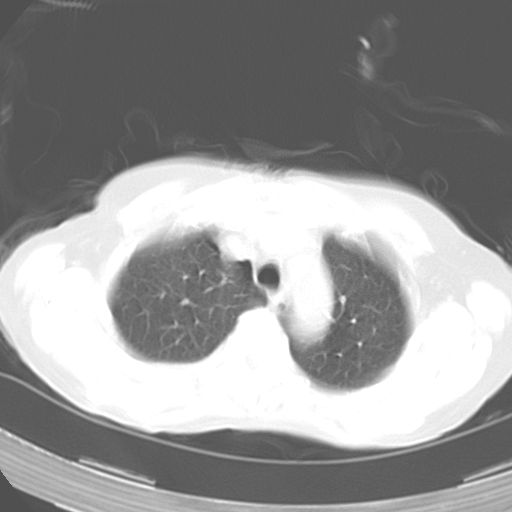

以下是引用dyqct在2006-12-7 21:08:00的发言:[br]考虑:1、肝内外胆管多发性结石伴肝左叶外侧段肝萎缩;[br] 2、右膈下多发脓肿;[br] 3、右侧少量胸腔积液、斜裂积液;[br] 4、左肾囊肿。

以下是引用jiazh在2006-12-7 20:37:00的发言:[br]肝脏周围半狐形低密度影,肝脏表面受压推移,考虑膈下脓肿可能性大;2、右侧胸腔积液

以下是引用拾荒者在2006-12-7 21:44:00的发言:[br]肝内外胆管多发结石,右膈下多发脓肿,右胸膜腔及叶间裂积液,左肾囊肿。[br] [br]